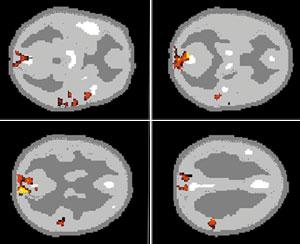

Очень важна проблема мозгового обеспечения внимания у человека. Ею в нашем институте занимается и моя лаборатория, и лаборатория Ю.Д.Кропотова. Исследования ведутся совместно с коллективом ученых под руководством финского профессора Р.Наатанена, который открыл электрофизиологические корреляты так называемого механизма непроизвольного внимания. Чтобы понять, о чем идет речь, представьте ситуацию: охотник крадется по лесу, выслеживая добычу. Но он и сам является добычей для хищного зверя, которого не замечает, потому что настроен только на поиск оленя или зайца. И вдруг случайный треск в кустах, может быть, и не очень заметный среди птичьего щебета и шума ручья, мгновенно переключает его внимание, подает сигнал: “рядом опасность”. Механизм непроизвольного внимания сформировался у человека в глубокой древности как охранный механизм, но работает и сейчас: например, человек ведет машину, слушает радио, слышит крики детей, играющих на улице, воспринимает все звуки окружающего мира, внимание его рассеянно, и вдруг тихий стук мотора мгновенно переключает его внимание на машину - он осознает, что с двигателем что-то не в порядке (кстати, это принципиально схожее с детектором ошибок явление). Такой переключатель внимания работает у каждого человека. Нами обнаружены ПЭТ корелляты этого механизма, а Ю.Д.Кропотовым - электрофизиологические корелляты у больных с имплантированными электродами. Смешное. Мы закончили эту работу перед очень важным и престижным симпозиумом. В спешке. Поехали туда, и там, где у нас двоих были доклады, мы с удивлением и «чувством глубокого удовлетворения» неожиданно заметили, что активация в одних и тех же зонах. Да, иногда двоим сидящим рядом надо поехать в другую страну, чтобы поговорить.

Активации первичной слуховой коры. Активации префронтальной коры. ПЭТ корреляты феномена негативности рассогласования (отражение первичной автоматической обработки слуховых стимулов). |

Что же мы получили? Исследованы ПЭТ корреляты неосознанного внимания, т.н. феномена негативности рассогласования - непроизвольное переключение внимания к девиантным акустическим стимулам. Проведены иследования негативности рассогласования при предъявлении как простых слуховых стимулов (тонов), так и более сложных: аккордов и фонем. При всех этих видах стимулов обнаружены сходные корреляты негативности рассогласования. Первый паттерн активаций расположен в верхневисочных отделах (слуховой коре) обоих полушарий, что указывает на реакцию на изменение тональности, даже незначительную, причем более выраженная активация височной коры имеет место, когда девиантные стимулы перемешаны со стандартными, чем при предъявлении только девиантных стимулов. Более выраженная активация присутствовала в правом полушарии, что соотвествует предшествующим электрофизиологическим данным. Второй паттерн - активации лобной доли, причем они присутствовали как при стимуляции только девиантными, так при сочетании стандартных и девиантных стимулов. В лобной доле имелись фокусы префронтальной активации, что тоже соотвествует предшествующим электрофизиологическим данным, а также в области средней и верхней лобной извилин. Также отмечались активации передних отделов поясной извилины и билатеральные активации задних теменных областей (правосторонняя теменная активация была описана при магнитоэнцефалографии). Активации лобной доли, скорее всего, лежат в основе сознательной уверенности субъекта в изменении стимула, который уже был неосознанно выделен слуховой корой обоих полушарий. Такая роль лобной доли как структуры, обеспечивающей переключение внимания, подтверждается выраженными паттернами активаций, которые вызываются девиантными тонами, когда их предъявляют в чистом виде с относительно длинными, нерегулярными интервалами, что известно из предыдущих исследований. Активации передних отделов поясной извилины и теменной коры могут включаться в мозговые механизмы переключения внимания. Дополнительно была выявлена активация коры островка Рейли, что не было известно по предыдущим электро- и магнитоэнцефалографическим исследованиям, но подобные активации были получены и по результатам прямой регистрации через вживленные электроды вызванных потенциалов с этих структур в лаборатории программирования действий ИМЧ РАН. Роль этой структуры в обеспечении процессов внимания в настоящее время неизвестна и подлежит дальнейшему изучению. Таким образом, были выявлены паттерны мозговых активаций, проливающие свет на механизмы, с помощью которых девиантные слуховые стимулы вызывают непроизвольное переключение внимания.

Кроме непроизвольного внимания есть еще и селективное. Так называемое внимание на коктейль приеме. Все говорят разом, а вы следите только за собеседником, подавляя неинтересную вам болтовню соседа справа. Похожая ситуация изображена на рисунке. В оба уха расказывают истории. Разные. В первом случае следим за историей в правом ухе, а во втром - в левом. Видно, как меняется активация областей мозга. Заметим, кстати, что активация на историю в правое ухо значительно меньше. Почему? А потому, что большинство людей берут телефон в правую руку и прикладывают его к правому уху. Поэтому следить за историей в правом ухе проще.

|

|

Латерализация мозгового обеспечения селективного внимания. Слева внимание на левое ухо, справа естественно на правое. Видно, что активированы различные зоны. |

|

|

Сравнение слухового и зрительного селективного внимания. В задании на левостороннее слуховое селективное внимание по сравнению со зрительным вниманием при дихотическом прослушивании и одновременном зрительном предъявлении различных текстов также определяется активация слуховой коры противоположного полушария, что, как и на предыдущем рисунке, отражает селективную настройку слуховой коры, не зависящую от вида и сложности предъявляемых стимулов. Процесс же подавления обработки иррелевантных, но значимых зрительных стимулов при слуховом внимании вызывает выраженные активации зрительной коры (затылок). |

Показано, что слуховое селективное внимание при бинауральной стимуляции избирательно активирует области височной коры, специфичные для слухового предъявления сигналов. Эти результаты согласуются с мировыми данными, подтверждая, что и степень выраженности этой полушарной латерализации также зависит от направления внимания. Наши данные указывают, что этот эффект латерализации (односторонности) сконцентрирован в первичной слуховой коре, причем селективное внимание к латерализованным звукам усиливает активность слуховой коры преимущественно в первичных слуховых зонах контрлатерально направлению подачи стимулов. То есть слуховая кора селективно настраивается в соответствии с направлением внимания, что обычно не определяется при экстракраниальной регистрации электрической или магнитной активности мозга. Наиболее вероятно, что имеющая место полушарная латерализация активации слуховой коры, ассоциирующаяся с пространственно сфокусированным слуховым вниманием, вызвана подготовительной настройкой на внимание левой и правой слуховой коры в соотвествии с направлением внимания, предшествующей предъявлению стимулов и происходящей при фокусировке пространственого внимания. Префронтальная кора представляется вовлеченной в контроль за вниманием, т.к. в ряде работ в ней было выявлено усиление локального мозгового кровотока и усиление электрической активности. В наших исследованиях усиление префронтальной активности, особенно в ее дорзолатеральном отделе, ассоциируется с контролем настройки внимания правой и левой слуховой коры, причем большая выраженность активаций в лобной области при слуховом по сравнению со зрительным селективным вниманием вызвана, скорее всего, большим когнитивным усилием для выполнения слуховой дискриминации, когда внимание должно было быть направлено на один из двух конкурирующих потоков стимулов, тогда как выполнение задания на зрительное внимание не требовало внутримодального селективного внимания. Таким образом, было показано: слуховая кора селективно настраивается в соотвествии с направлением внимания. Эта настройка контролируется префронтальным исполнительным механизмом, что проявляется усилением префронтальной активности при слуховом селективном внимании.